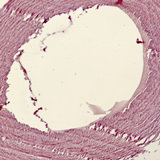

Smooth muscle and endothelial cells from a pigeon aorta

50x zoom